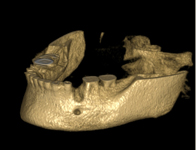

Při ztrátě molárů a premolárů v horní čelisti a jejich náhradě implantáty se často setkáváme s nedostatečnou

vertikální nabídkou kosti pod čelistní dutinou, často doprovázenou i nedostatečnou horizontální nabídkou a sníženou kvalitou kosti (v oblasti 2. premoláru v 50%, v oblasti moláru až v 80% případů nedostatečná kostní nabídka)

Od roku 1985 je tento problém řešen augmentační operací nazývanou

sinus lift.

Jedná se o vyzvednutí membrány, která čelistní dutinu vystýlá, pod vyzvednutou membránou vznikne kapsa, kam se umístí augmentační materiál, do kterého se zavedou implantáty.